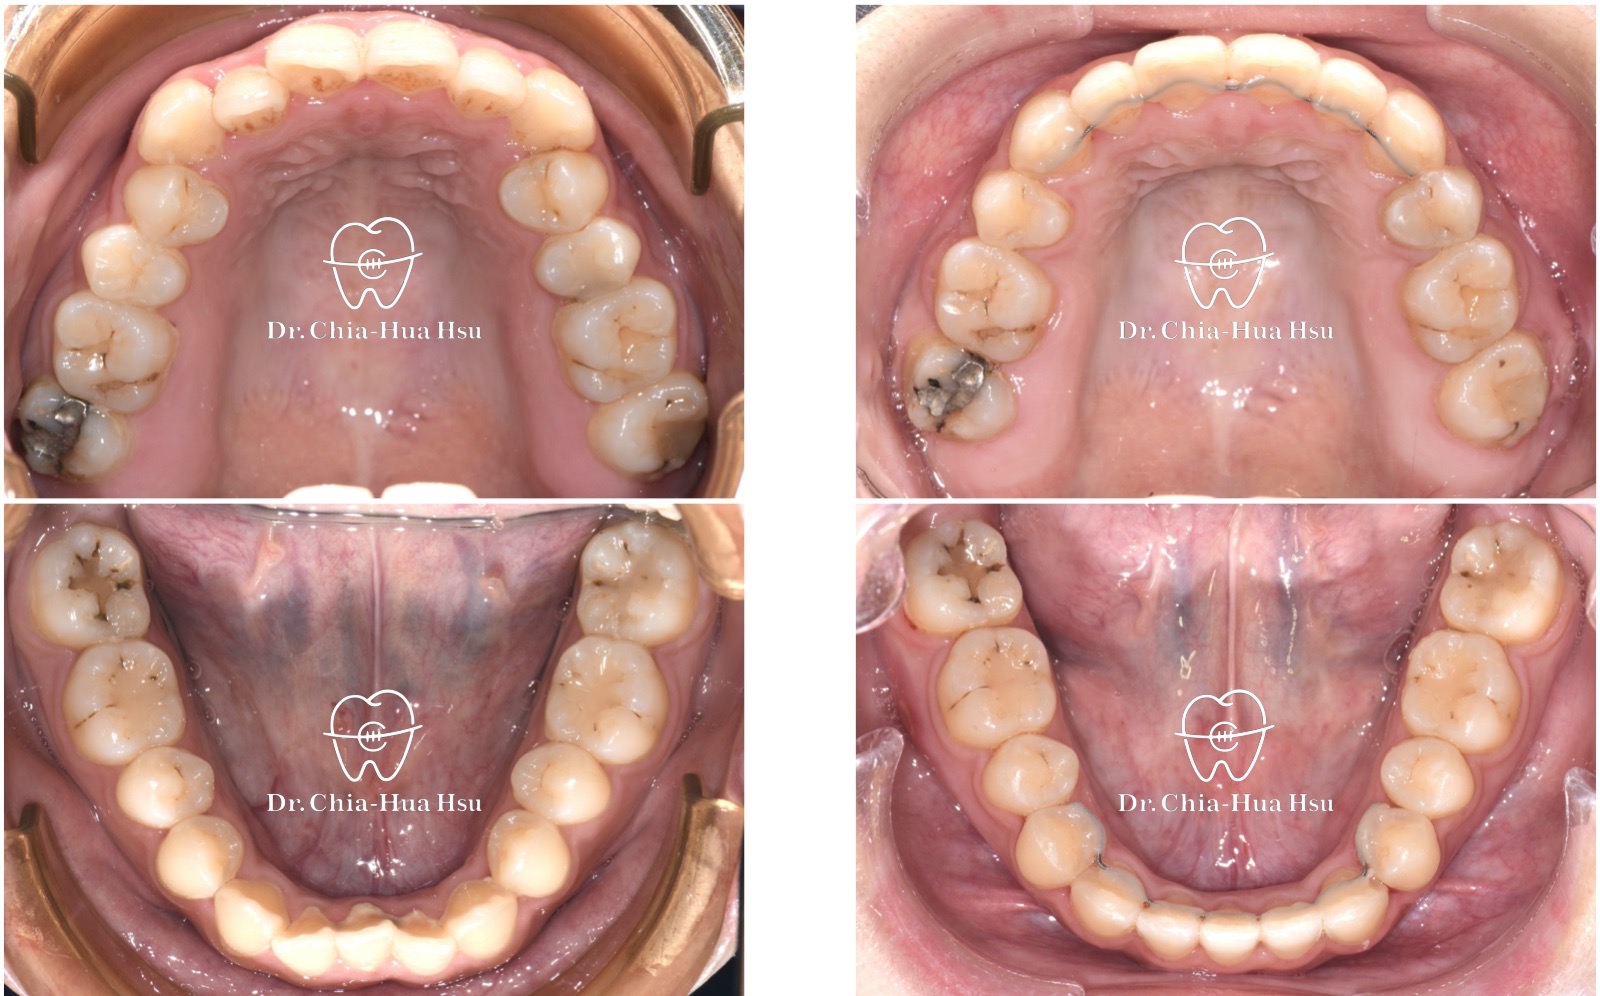

治療前

治療後